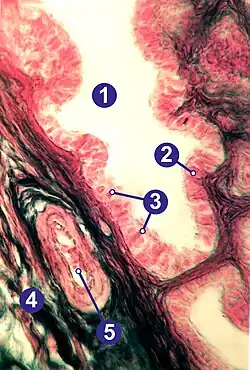

Histología

La pared de las trompas en su cara interna (luminal) es compleja. La mucosa está dispuesta sobre pliegues longitudinales denominados "plicas".

La estructura histológica varía en los diferentes segmentos, lo que permite una funcionalidad adaptada en cada uno. Se observan tres capas tisulares diferentes mucosa (endosalpinge), muscular (miosalpinge) y serosa, sus proporciones varían en los distintos segmentos.[12][13]

Internamente, cada oviducto está cubierto de una mucosa con pliegues ("plicas"), con un epitelio cilíndrico pseudoestratificado con células ciliadas, células caliciformes y células no ciliadas intercalares (o peg). Las células epiteliales descansan sobre una lámina basal y una lámina propia conjuntiva laxa subyacente.

La capa media contiene músculo liso, donde se puede distinguir una capa circular interna y otra longitudinal externa.

La capa más externa consiste en la serosa de epitelio simple plano, con tejido conectivo subyacente donde se pueden observar grandes vasos sanguíneos y nervios.